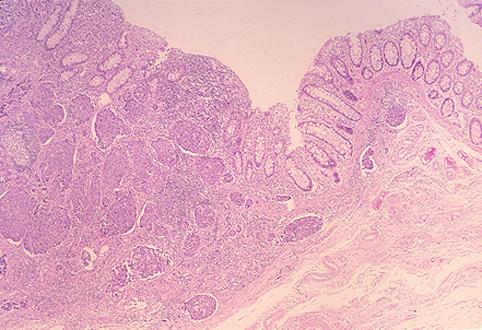

질환(병리주체)의 분류 악성 상피성종양/미분화암

부위(장기별) 대장/직장

검사방법 마이크로

종양의 육안분류 1형(종괴형)/

종양의 최대경(밀리미터) 40이상

종양의 심달도 mp